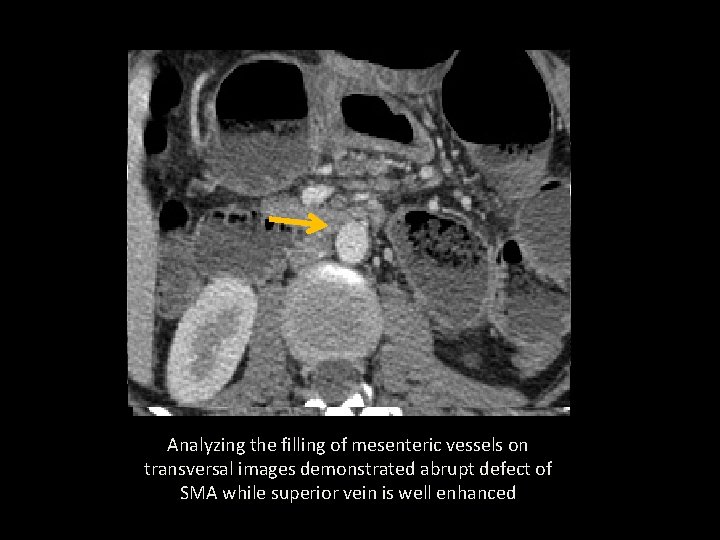

Analyzing the filling of mesenteric vessels on transversal images demonstrated abrupt defect of SMA while superior vein is well enhanced